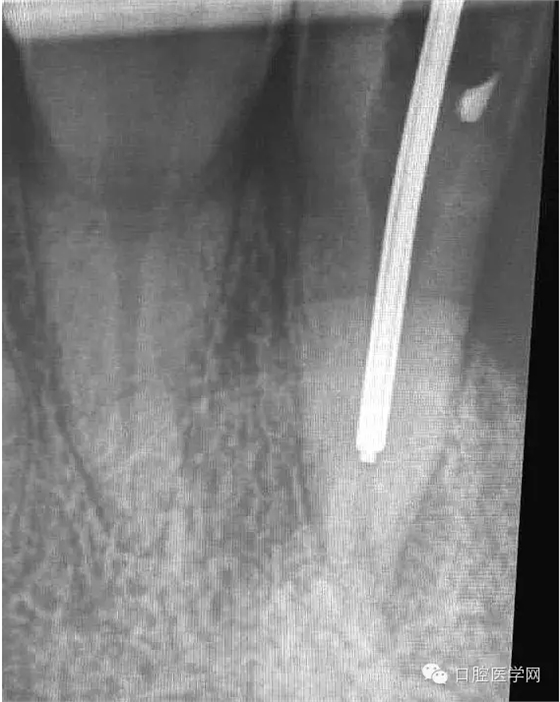

3.十天之后復(fù)診,無明顯癥狀,。準(zhǔn)備再次用2.5%次氯酸鈉+2%氯己定+17%EDTA交替沖洗,在用超聲蕩洗。

4.準(zhǔn)備放置橡皮障(由于拍片是較遠(yuǎn),所以,橡皮章暫時(shí)取下),去除暫封材料。在顯微鏡放大視野中,蔣調(diào)拌好MTA輸送至根尖部。